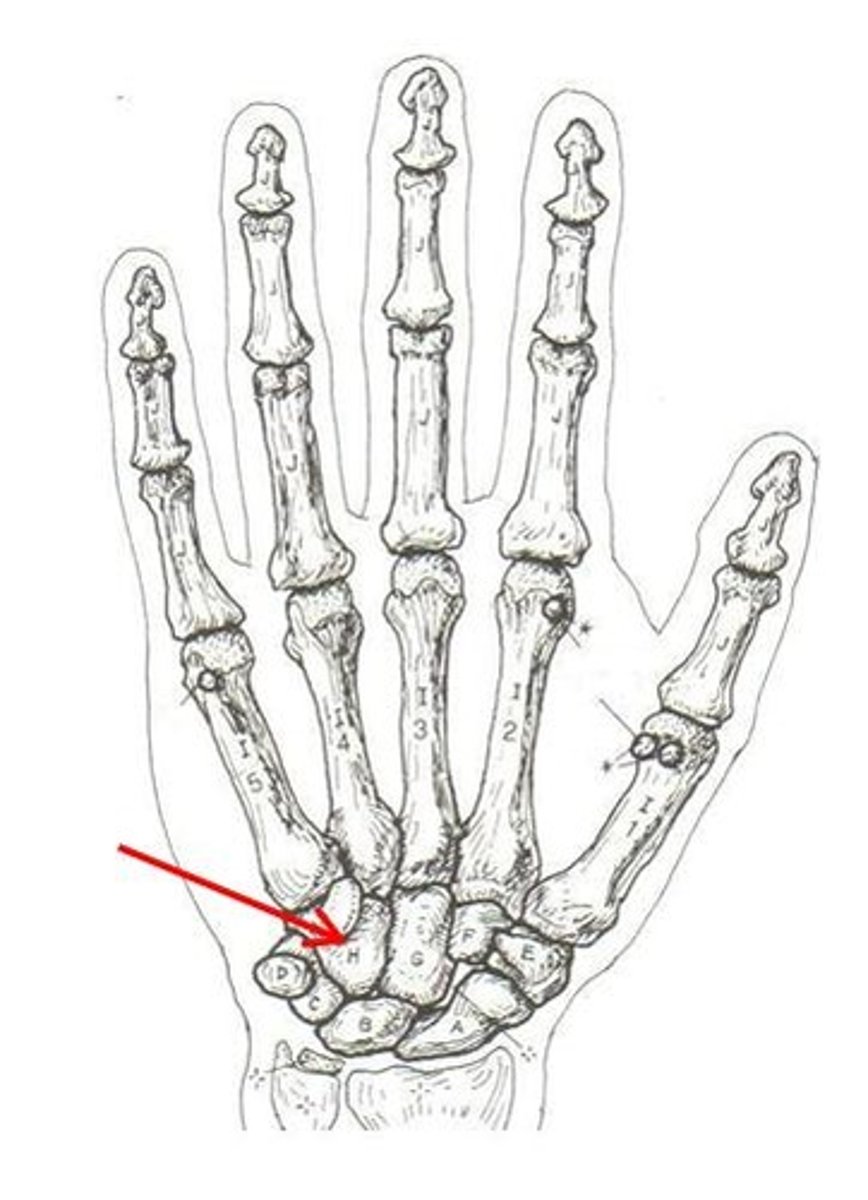

carpals

ID group

scaphoid

ID bone

lunate

ID specific bone

scaphoid

ID specific bone

pisiform

ID specific bone

triquetrum

ID specific bone

trapezium

ID specific bone

capitate

ID specific bone

hamate

ID specific bone